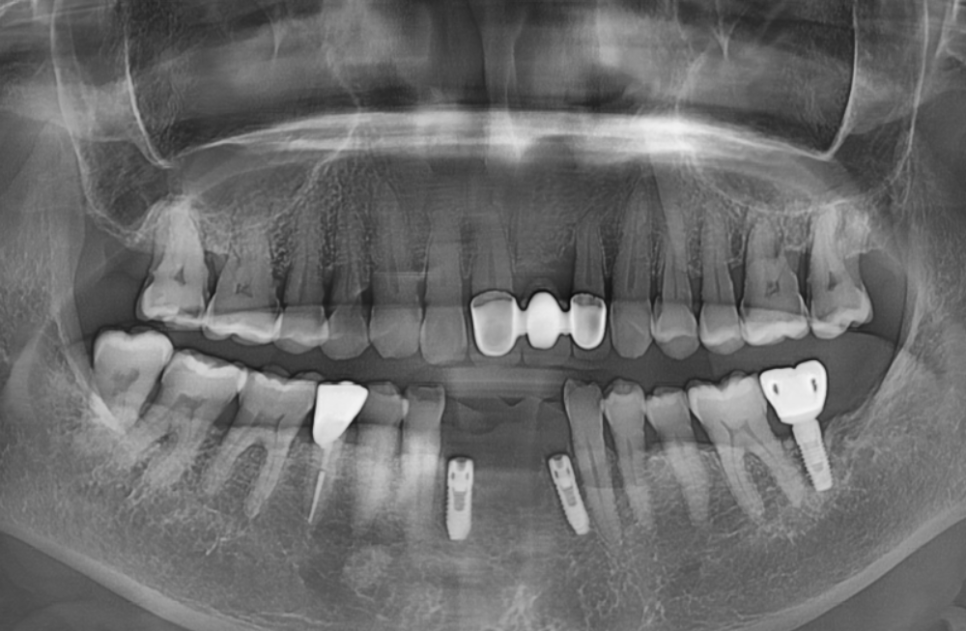

이번 환자분의 경우,

CT 분석 결과 남아 있는

뼈의 양과 밀도가

임플란트를 식립하기에 충분했습니다.

그래서 뼈이식 없이

발치 당일 즉시 임플란트를 식립하는

방식으로 진행했습니다.

230609

그로부터 5개월 뒤,

임플란트와 뼈가 잘 붙었는지

수치로 확인하고 나서야

기분 좋게 본을 뜰 준비를 시작했습니다.